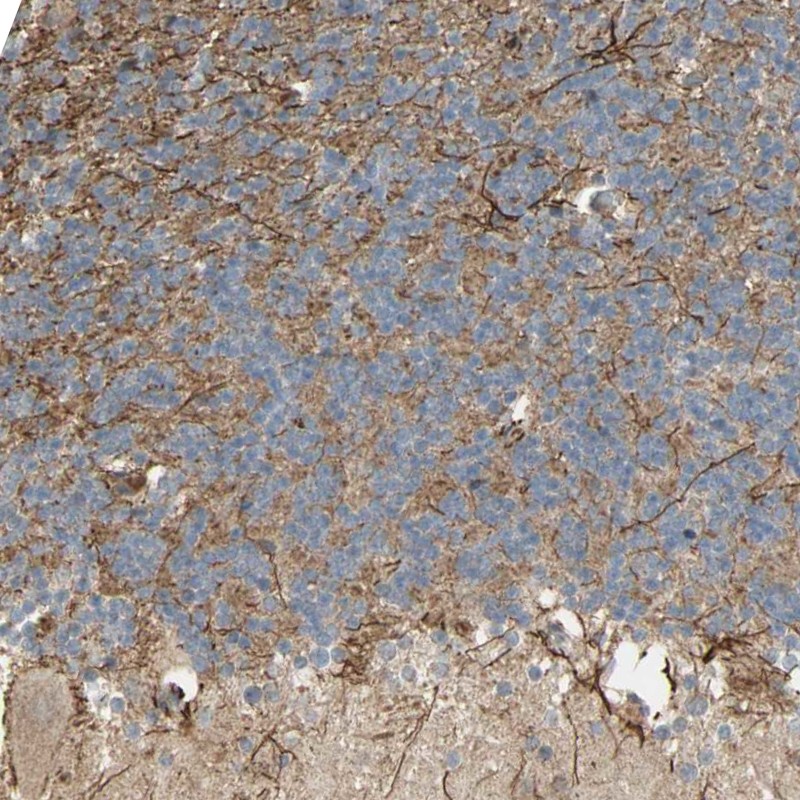

Immunohistochemical staining of human cerebellum shows strong cytoplasmic positivity in processes.